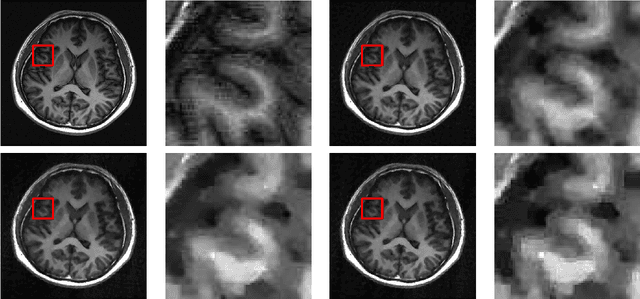

In compressive sensing, it is challenging to reconstruct image of high quality from very few noisy linear projections. Existing methods mostly work well on piecewise constant images but not so well on piecewise smooth images such as natural images, medical images that contain a lot of details. We propose a two-stage method called GeoCS to recover images with rich geometric information from very limited amount of noisy measurements. The method adopts the shearlet transform that is mathematically proven to be optimal in sparsely representing images containing anisotropic features such as edges, corners, spikes etc. It also uses the weighted total variation (TV) sparsity with spatially variant weights to preserve sharp edges but to reduce the staircase effects of TV. Geometric information extracted from the results of stage I serves as an initial prior for stage II which alternates image reconstruction and geometric information update in a mutually beneficial way. GeoCS has been tested on incomplete spectral Fourier samples. It is applicable to other types of measurements as well. Experimental results on various complicated images show that GeoCS is efficient and generates high-quality images.